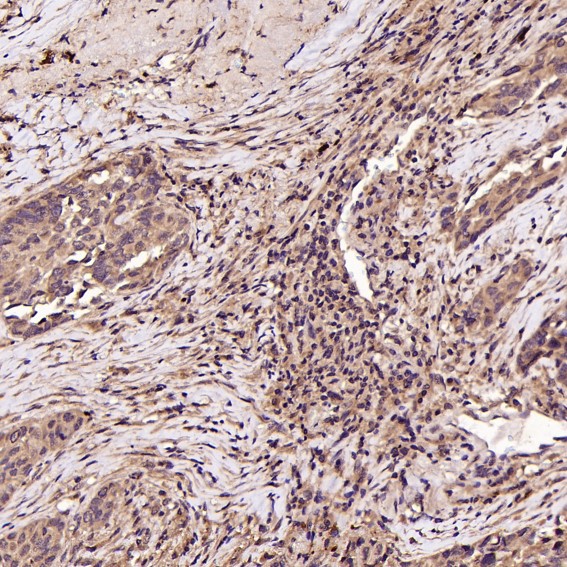

Isoform 1 and isoform 2 are expressed in platelets and megakaryocytes, but not in reticulocytes. Not detected in Jurkat, nor in U937 cell lines (PubMed:2351656). Isoform 3 is expressed in prostate adenocarcinoma, as well as in several erythroleukemia, prostate adenocarcinoma and melanoma cell lines, including PC-3, DU-145, HEL, WM983A, WM983B and WM35. Not detected in platelets, nor in normal prostate (at protein level) (PubMed:9809974).